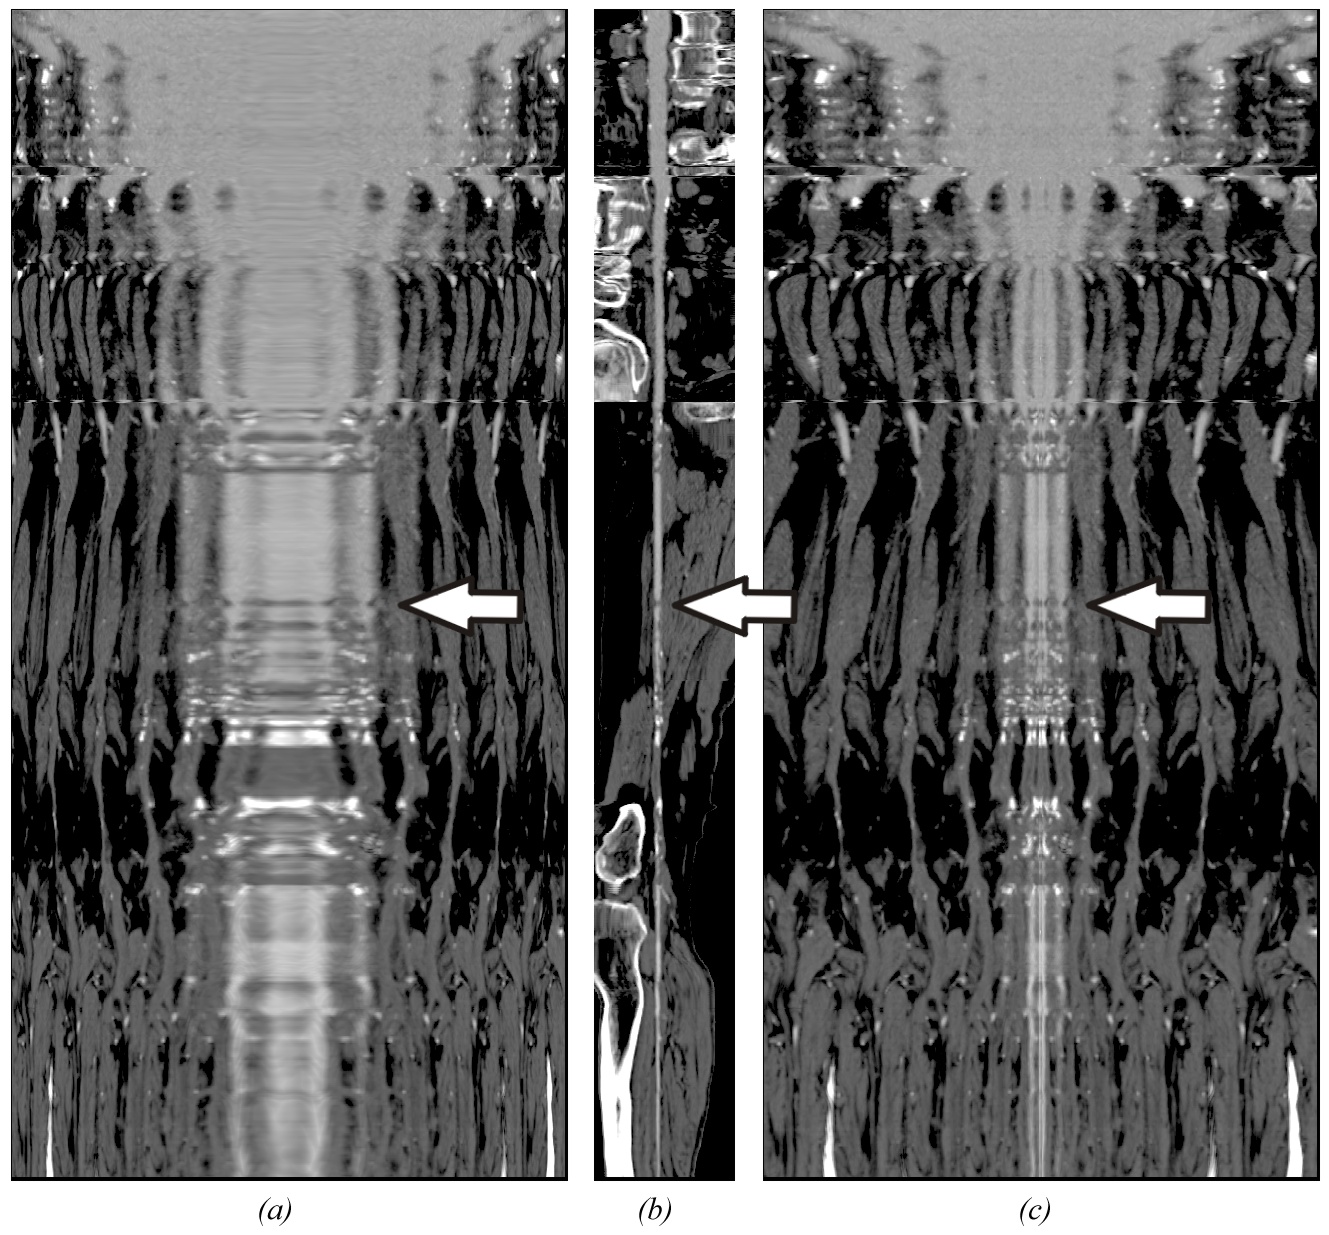

Traditional volume visualization techniques may provide incomplete clinical information needed for many applications in medical visualization. Especially in the area of vascular visualization important features such as the patent lumen of a diseased vessel segment may not be visible. Curved Planar Reformation (CPR) has proven to be an acceptable practical solution. Existing CPR techniques, however, still have diagnostically relevant limitations. In this paper we introduce two advanced methods for efficient vessel visualization, based on the concept of CPR. Both methods benefit from relaxation of spatial coherence in favor of improved feature perception. We present a new technique to visualize the interior of a vessel in a single image. A vessel is re-sampled along a spiral around the vessel central axis. The helical spiral depicts the vessel volume. Furthermore, a method to display an entire vascular tree without mutually occluding vessels is presented. Minimal rotations around the branching points of a vessel tree eliminate occlusions. For each viewing direction the entire vessel structure is visible.Keywords: computed tomography angiography, vessel analysis, curved planar reformation

Armin Kanitsar, Rainer Wegenkittl, Dominik Fleischmann, Meister Eduard Gröller, "Advanced Curved Planar Reformation: Flattening of Vascular Structures", submitted to IEEE Visualization 2003, AKanitsar_Adv.pdf (2.371KB).Figures in the paper